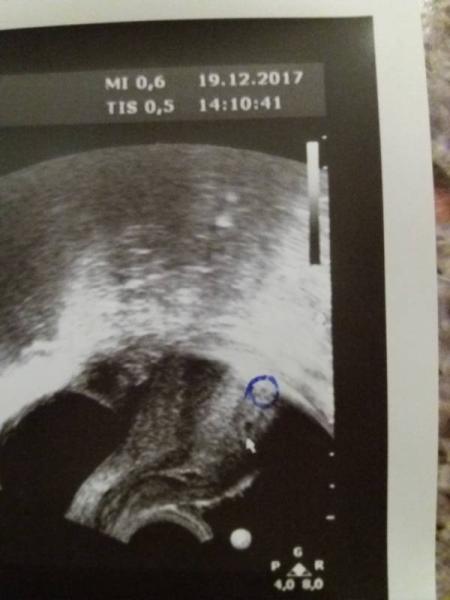

Erster Ultraschall nach Icsi bei 4+5 Was hat man bei euch gesehen?

Bild zu Ultraschall nach Icsi - Kinderwunschbehandlung

Huhu bei 4+5 kann man leider nichts anderes sehen als eine Fruchthöhle. Eine Woche später kann man meistens schon den Embryo sehen und in der 7 Ten Woche oft den Herzschlag Alles gute